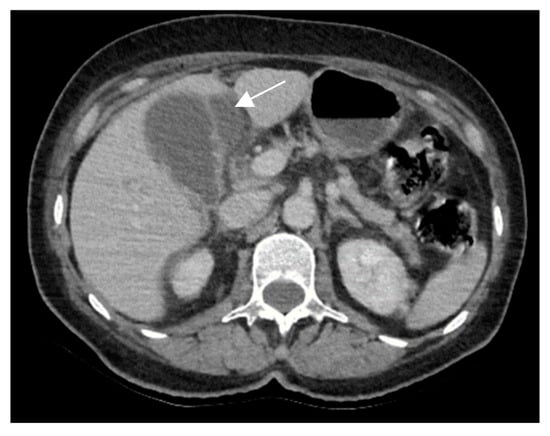

A 69-year-old female patient with a past medical history of diabetes type II presented to the Emergency Department with a 2-day upper abdominal pain, accompanied by hypotension and oligoanuria. Routine laboratory evaluation showed elevated inflammatory markers (leukocytosis, procalcitonin 100 ng/mL, CRP 126 mg/L), elevated transaminases and ferritin. The patient underwent contrast-enhanced computed tomography (Figure 6). CT images depicted a distended gallbladder (99 mm in longitudinal measurement), with asymmetrical thick-walled gallbladder (16 mm), heterogeneous contrast enhancement (Panel A), with a gallbladder neck stone (10 mm), extended to the duodenum (Panel B and Panel C). CT showed multiple low-attenuation hepatic masses with peripheral enhancement, adjacent to the gallbladder fossa (segment V) and intrahepatic biliary tract dilatation. Below the liver and adjacent to the gallbladder fundus, fat standing and free fluid were observed. These imaging findings were suggestive of acute cholecystitis complicated by an intrahepatic abscess or gallbladder carcinoma with wall perforation into the adjacent liver.

Figure 6. Multiplanar sections of contrast-enhanced CT acquisitions richly illustrating gallbladder carcinoma with an associated necrotizing infectious component. (A,B). Distended gallbladder with asymmetrical thick-walled gallbladder (16 mm) (white arrow). (C,D). Abscess adjacent to the gallbladder (black arrow); extension to the duodenum (blue arrow).